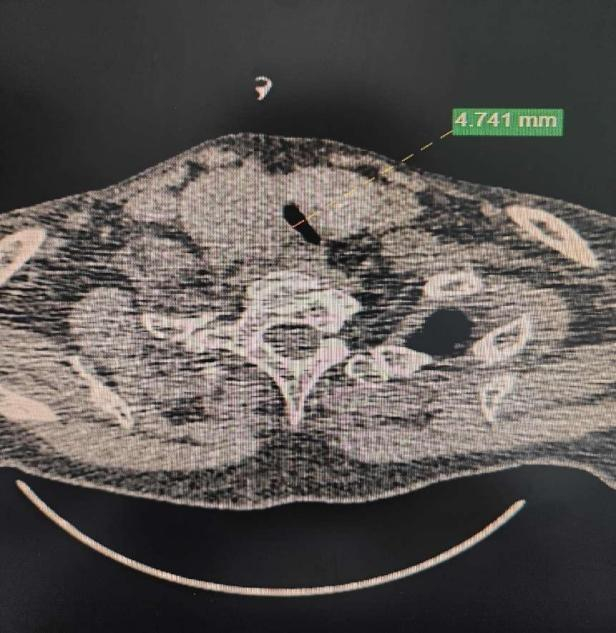

在急诊进行了初步处理,维持通气之后,CT检查结果显示王阿姨甲状腺肿已经向下长入胸骨后的胸腔纵隔内,前方顶住胸骨、后方顶住颈胸椎,最下方已达心脏大血管,挤压气管,气管目前已经极度狭窄,现在一口痰都可能会导致她出现窒息的情况。

经过详细检查后结果显示王阿姨的气管已明显受到甲状腺肿瘤的压迫,最窄处仅4mm多一点,必须尽快进行手术。但令人担忧的是,王阿姨是一位合并有高血压、糖尿病、冠心病,曾因肺部肿瘤行肺癌手术治疗及肺储备功能下降的高龄患者,并且在口服氯吡格雷治疗中,对于麻醉、手术及围手术期管理等方面,手术带来的风险和压力都是极大的。